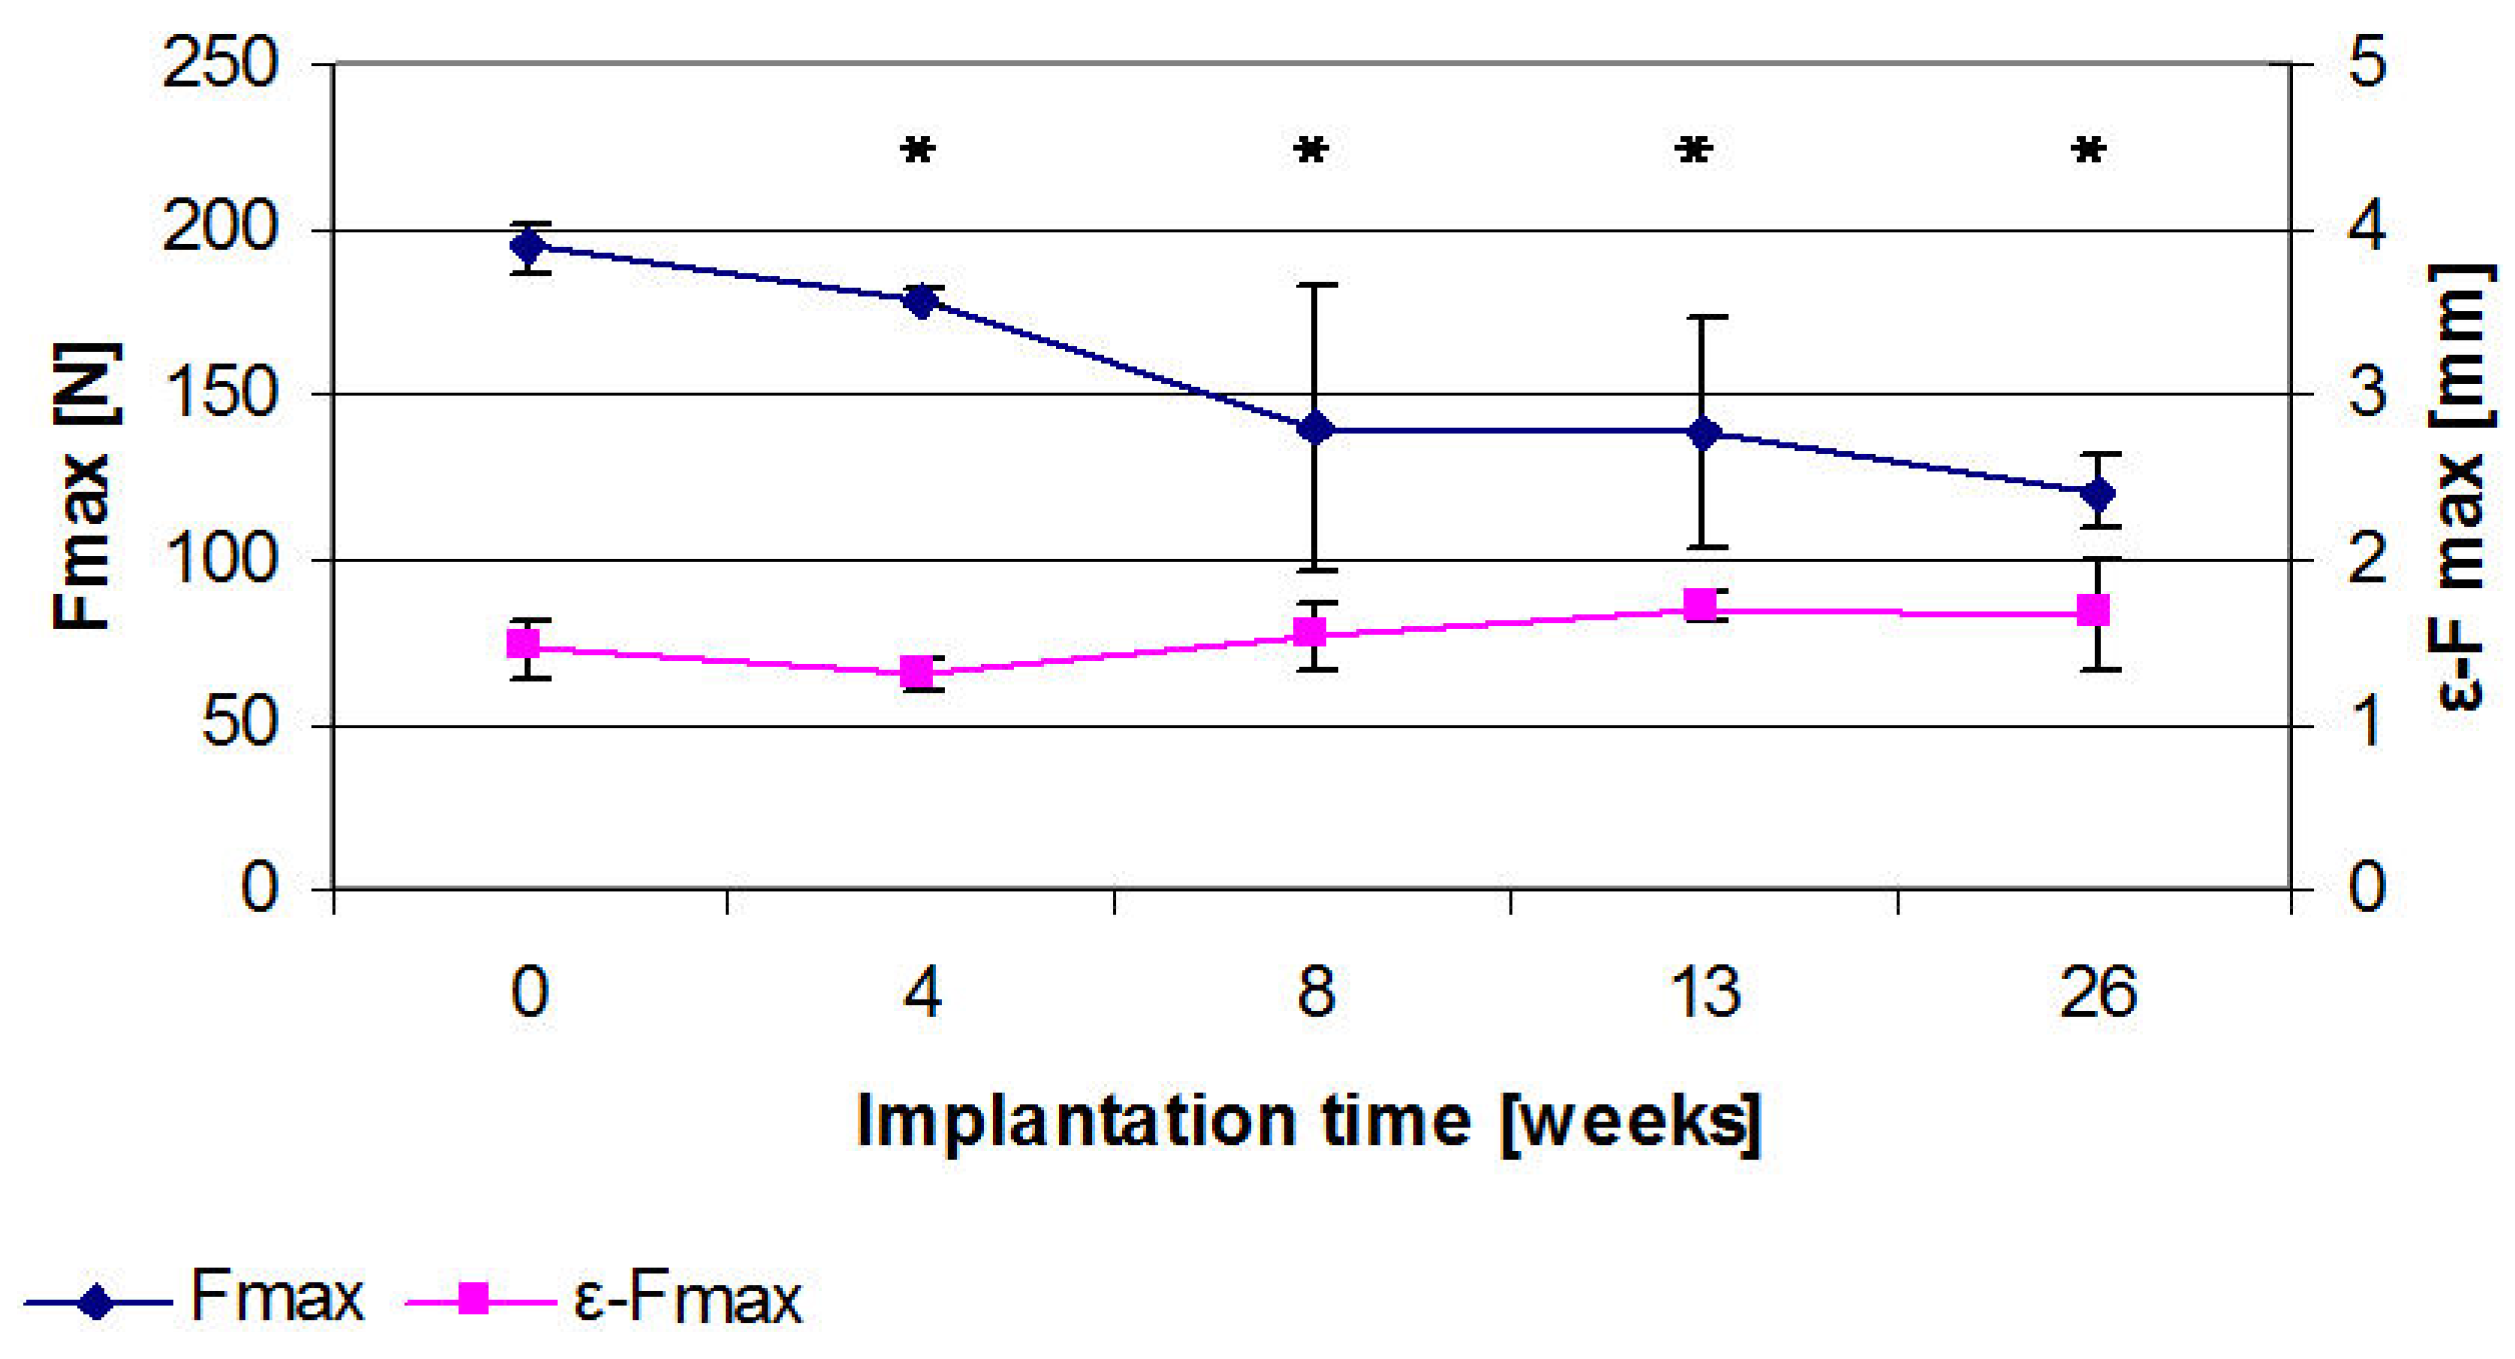

2.8. Results of the Three Point Bending